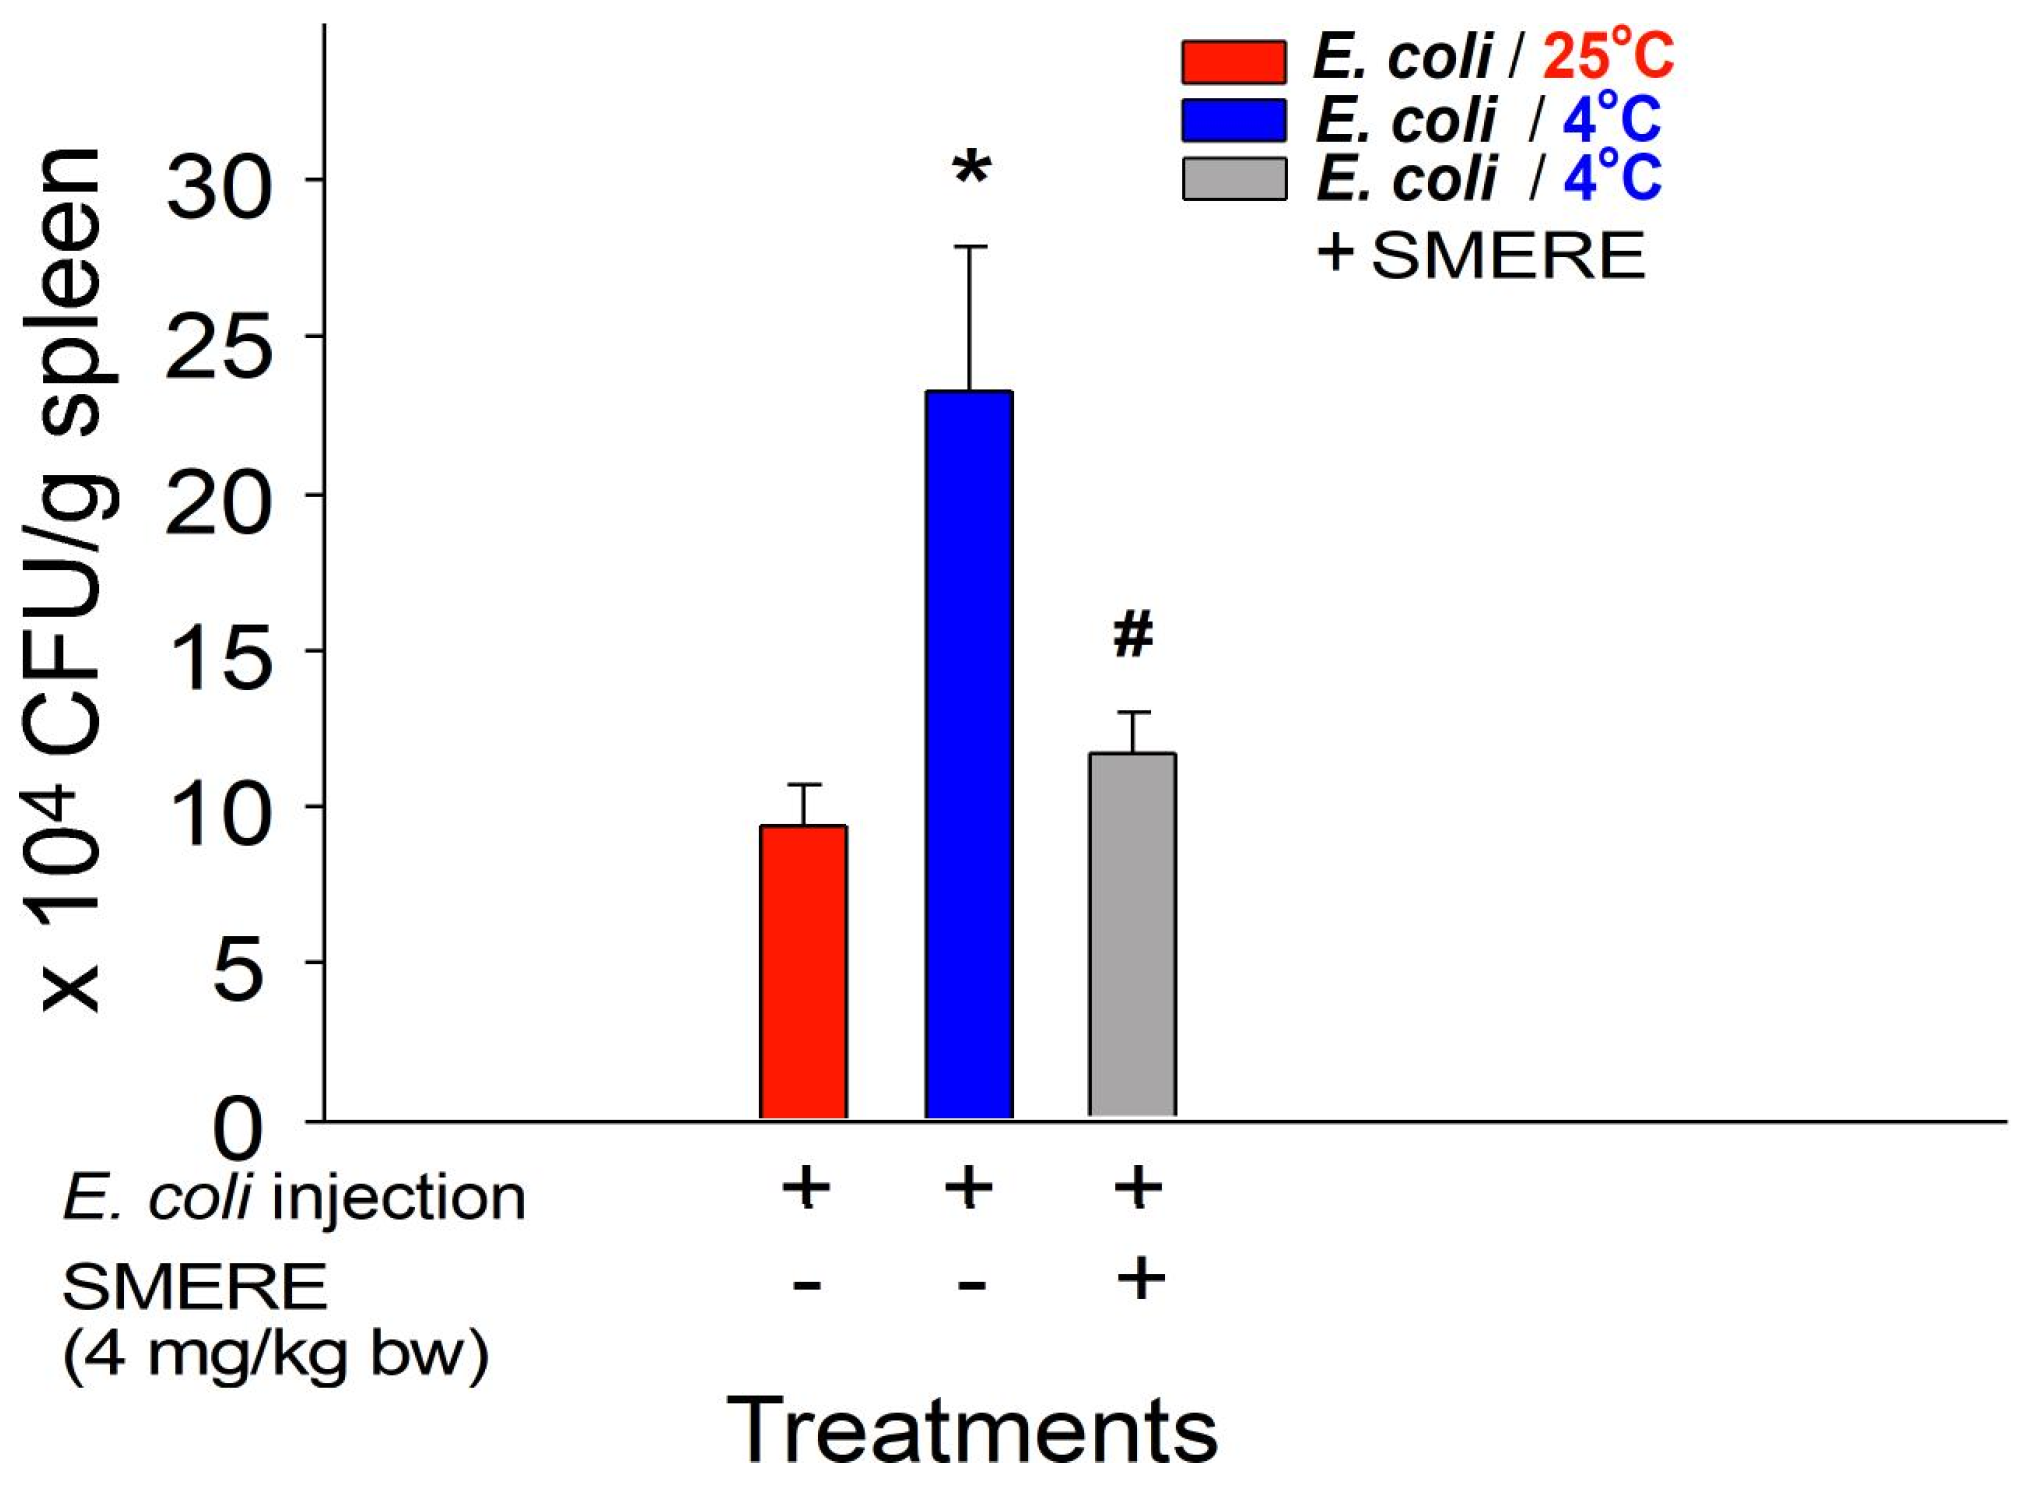

1. Introduction

2. Results

2.3. Reversal of Cold-Induced Immunosuppression through Treatment with SMERE in Mice

4. Materials and Methods

4.4. Analysis of Bacterial Clearance in the Cold Exposure Mouse Model